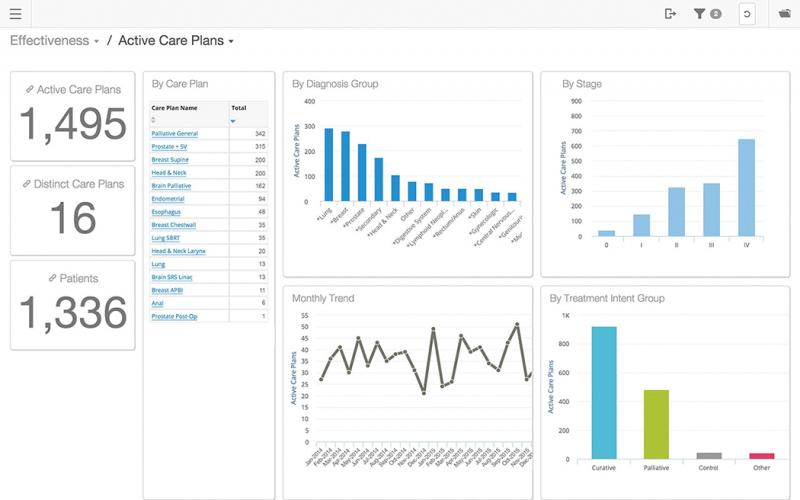

In 2016, the America Cancer Society expected 1,685,210 new cancer diagnoses in the United States alone. And according to the National Cancer Institute, approximately half of all patients diagnosed with cancer will undergo radiation therapy as part of their treatment plan. Given the large number of patients turning to radiation oncology, it is no wonder there is an immense focus on continually advancing this treatment technique. Millions of lives depend upon it.